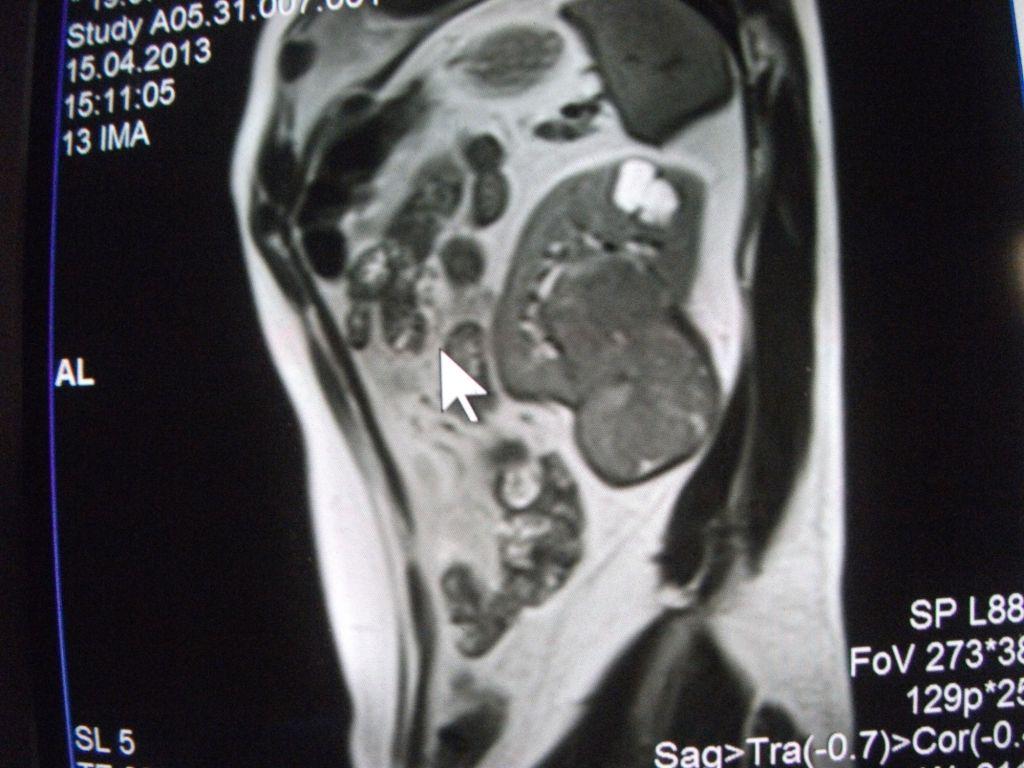

такое заключение: Левая почка: расположена обычно, увеличена, общими размерами около 13х5,5см. В области средней и нижней трети почки определяется объёмное образование неправильной формы, деформирующее наружный контур почки, распространяющиеся с чашечно-лоханочную систему. Опухоль имеет четкие неровные бугристые контуры с наличием псевдокапсулы, неоднородной структуры с признаками распада, максимальными размерами около 78,7х47х48мм

Вопрос такой: можно ли обойтись без удаления почки, удалив только опухоль.

Технически можно. Но практически - лучше нефрэктомия.